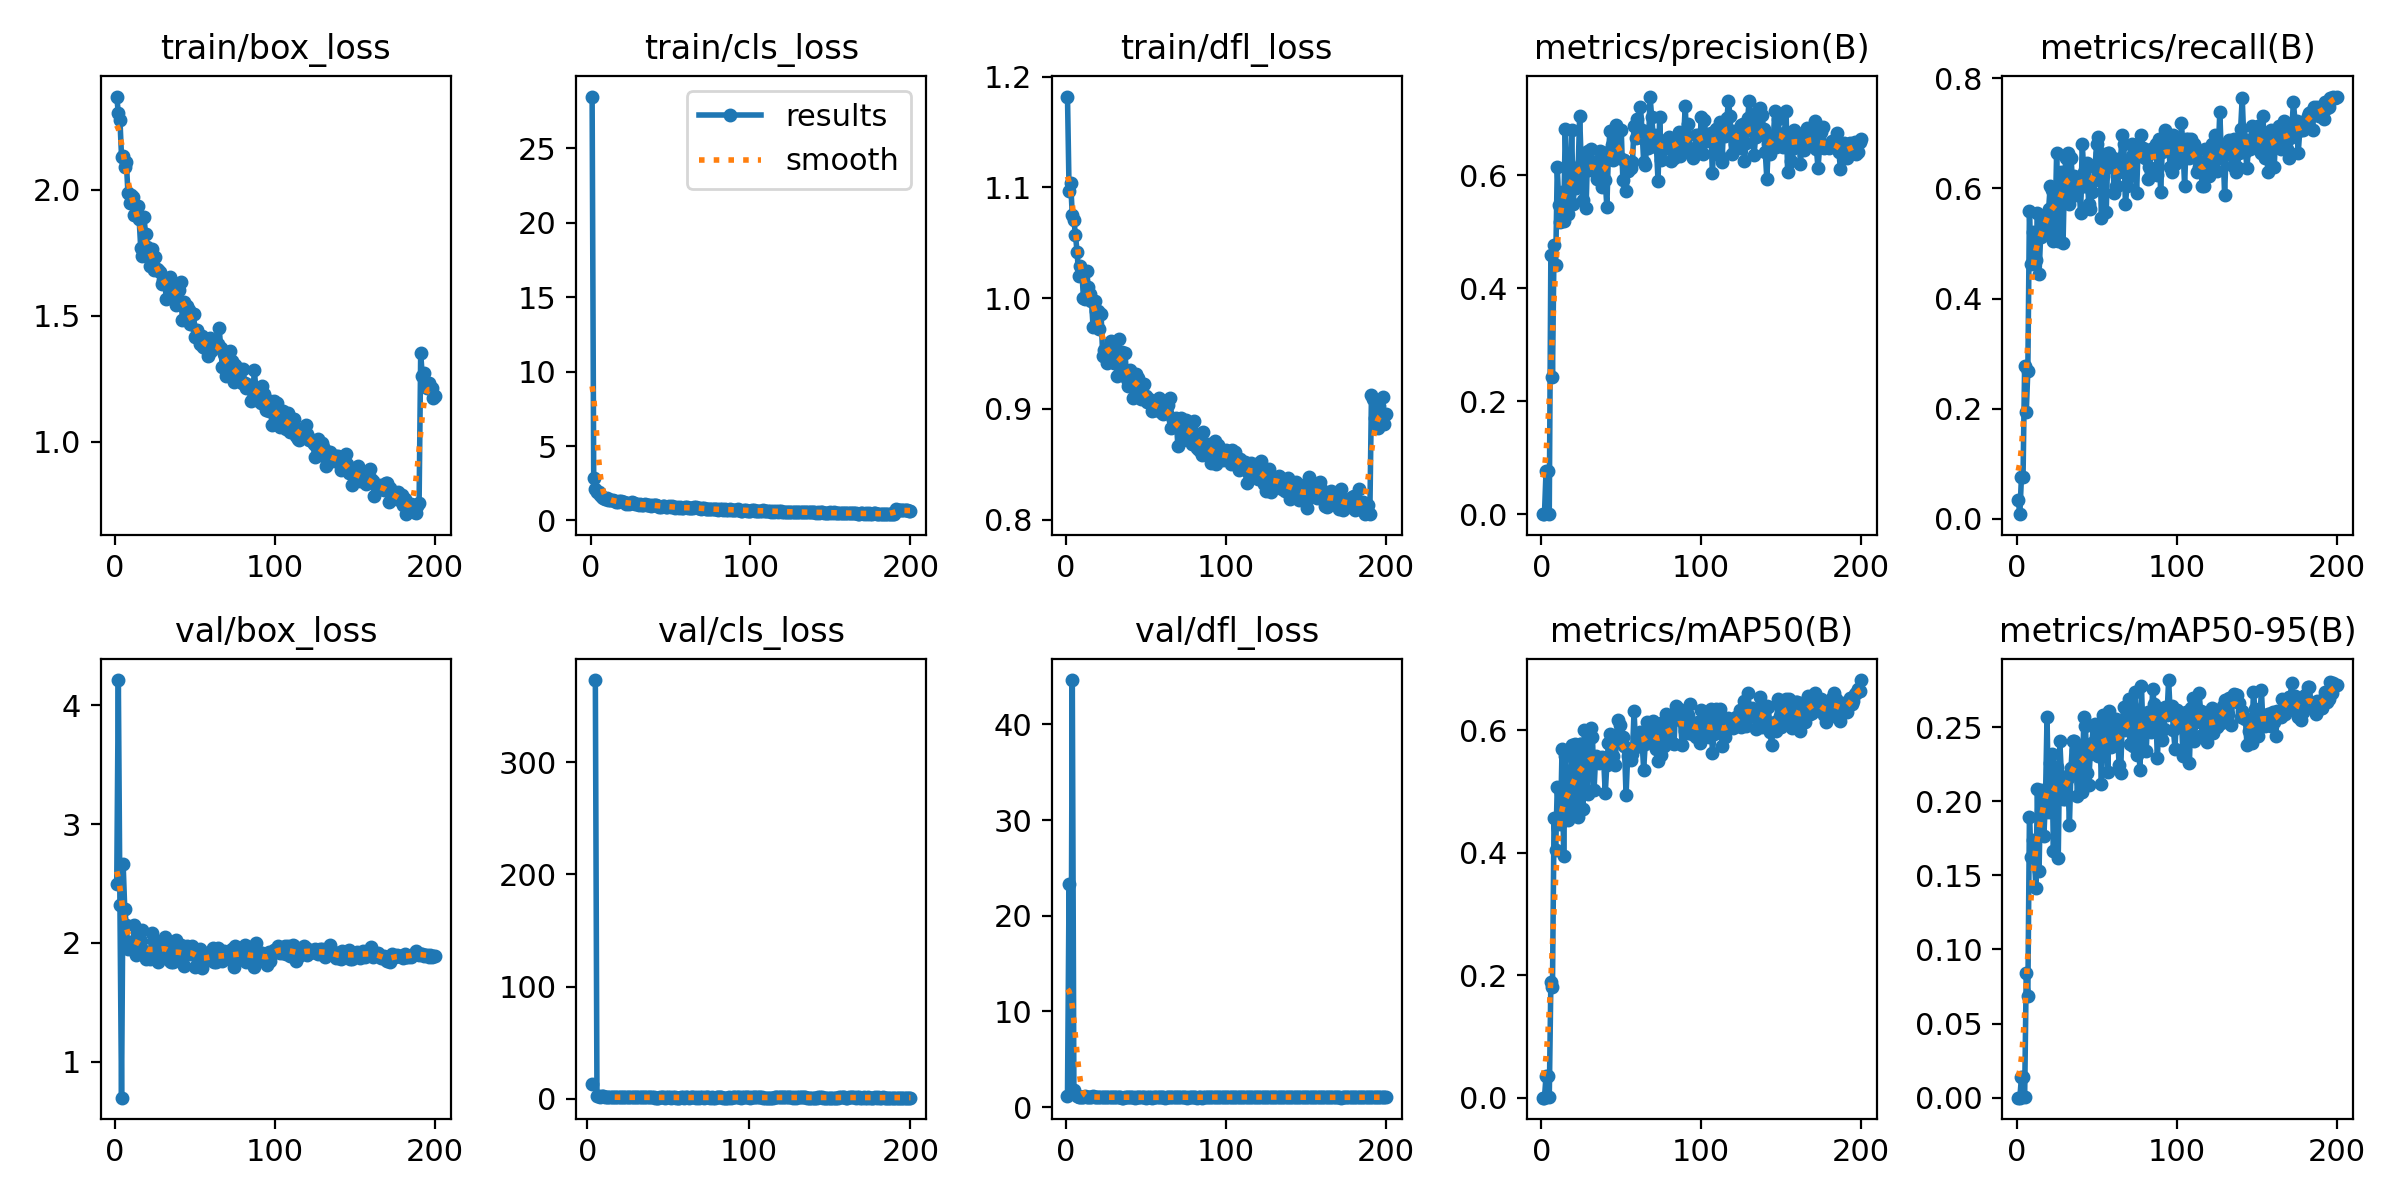

实验结果的指标图均保存在runs目录下, 大家只需要对实验过程和指标图的结果进行解析即可。

如果只指标图的定义不清晰,请看这个位置:YOLO11模型指标解读-mAP、Precision、Recall_yolo11模型训练特征图-CSDN博客

train/box_loss(训练集的边界框损失):随着训练轮次的增加,边界框损失逐渐降低,表明模型在学习更准确地定位目标。

train/cls_loss(训练集的分类损失):分类损失在初期迅速下降,然后趋于平稳,说明模型在训练过程中逐渐提高了对肺结节的分类准确性。

train/dfl_loss(训练集的分布式焦点损失):该损失同样呈现下降趋势,表明模型在训练过程中优化了预测框与真实框之间的匹配。

metrics/precision(B)(精确度):精确度随着训练轮次的增加而提高,说明模型在减少误报方面表现越来越好。

metrics/recall(B)(召回率):召回率也在逐渐上升,表明模型能够识别出更多的真实肺结节。

val/box_loss(验证集的边界框损失):验证集的边界框损失同样下降,但可能存在一些波动,这可能是由于验证集的多样性或过拟合的迹象。

val/cls_loss(验证集的分类损失):验证集的分类损失下降趋势与训练集相似,但可能在某些点上出现波动。

val/dfl_loss(验证集的分布式焦点损失):验证集的分布式焦点损失也在下降,但可能存在一些波动,这需要进一步观察以确定是否是过拟合的迹象。

metrics/mAP50(B)(在IoU阈值为0.5时的平均精度):mAP50随着训练轮次的增加而提高,表明模型在检测任务上的整体性能在提升。

metrics/mAP50-95(B)(在IoU阈值从0.5到0.95的平均精度):mAP50-95的提高表明模型在不同IoU阈值下的性能都在提升,这是一个更严格的性能指标。